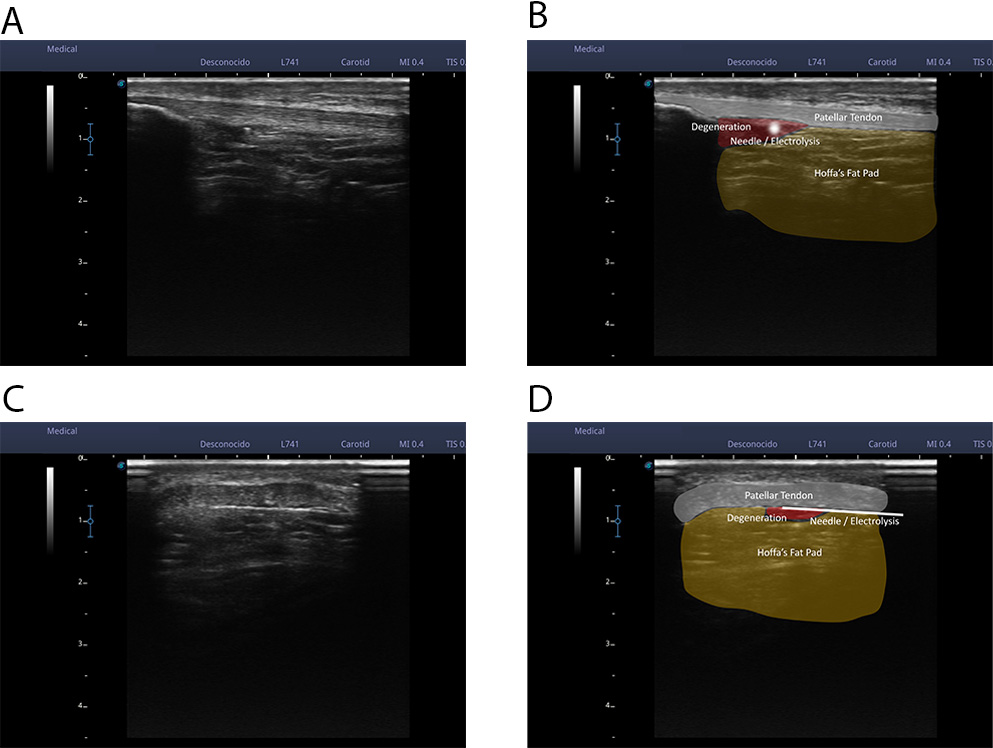

Three of the patients presented ultrasound images compatible with degenerative tendinopathy at the deep tendon interface in the area closest to the proximal insertion, as shown in Fig. 1A–C.

Fig. 1.

Fig. 1.Ultrasound images compatible with degenerative tendinopathy. (A) In the image we can observe an evident thickening of the patellar tendon in a longitudinal cut. (B) In the image we can appreciate a series of hypo-echoic images and tissue heterogeneity in the inner pole of the patella in a longitudinal cut. (C) In the image we can observe the presence of intratendinous neovascularization in a longitudinal cut. (D) Regional anatomy details.

In all cases the tendon approaches were superficial, on it superficial interface

and on it deep interface due to the relationship with the Hoffa fat. The needle

insertion area was sterilized with chlorhexidine. Sterile ultrasound gel was then

applied to obtain the reference ultrasound image. Ultrasound examination was then

performed until a clear cross-sectional image of the destructured area or the

area of local pain of the patellar tendon was obtained. Once the image was

obtained, using the scale to the left of the ultrasound image, the distance of

the superficial and deep interface of the patellar tendon from the probe was

calculated. With these reference values, the needle was introduced completely

parallel to the probe (in in-plane approach), from the lateral margin of the

tendon at the necessary distance to access the superficial or deep interface of

the tendon (Figs. 1,2). We use the electromedical device EPTE System, to supply

in each approach a galvanic current with 350

Fig. 2.

Fig. 2.An ultrasound examination was performed until a clear cross-sectional image of the unstructured area or the area of local pain of the patellar tendon was obtained. Once the image was obtained, using the scale to the left of the ultrasound image, the distance of the superficial interface and the deep interface of the patellar tendon from the probe was calculated. With these reference values, the needle was introduced completely parallel to the probe (an in-plane approach), from the lateral margin of the tendon at the necessary distance to access the superficial interface or the deep interface of the tendon (A,B). In these 2 images we can see a real image of an ultrasound cross-section of the patellar tendon (A) and a representation of the tissues that can be observed (B); patellar tendon, Hoffa fat, hypo-echoic area, and needle. (C,D) In these 2 images we can see a real image of a longitudinal ultrasound cut of the patellar tendon (C) and a representation of the observable tissues (D); patellar tendon, Hoffa fat, hypoechoic area, and needle.